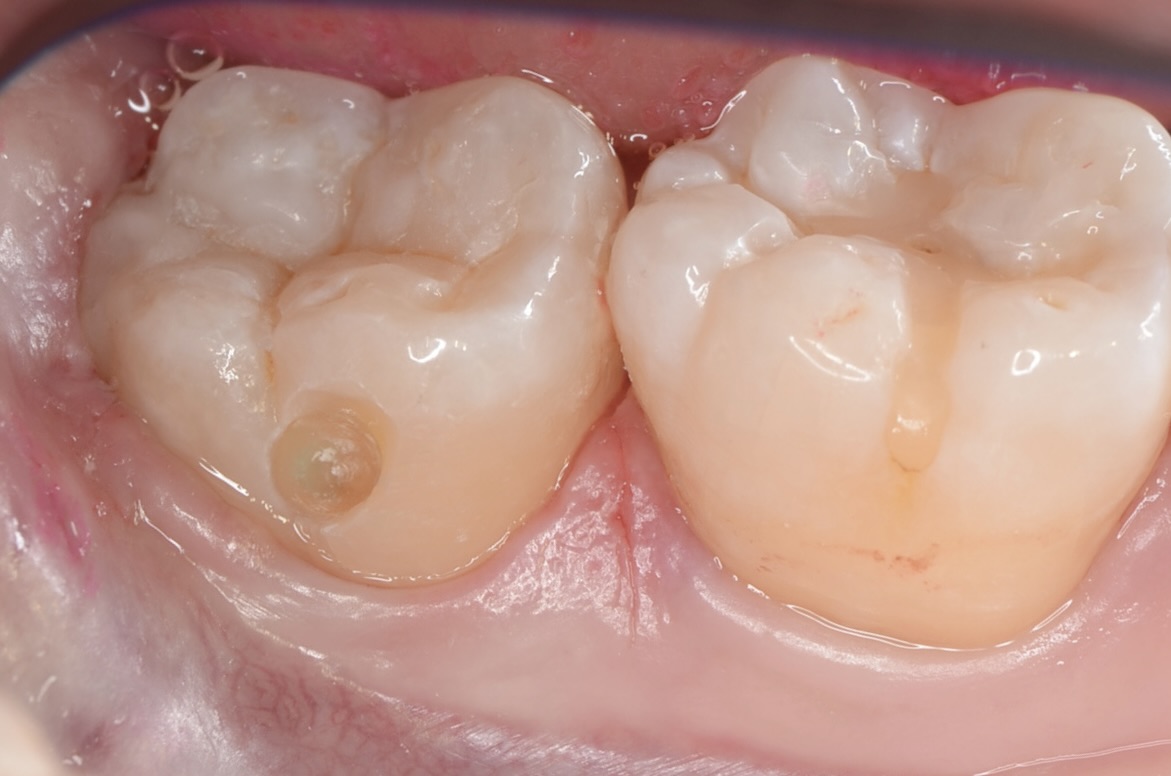

少しだけエナメル質を削ったところ

内部に虫歯が広がっているのを確認できました。 -

虫歯除去

虫歯を完全に削りました。小さな穴に見えても、虫歯は歯の中で広がっていることが多いです。 -

知覚過敏抑制材

虫歯は神経すれすれでしたが、露髄はしなかったので知覚過敏抑制材を象牙質にすり込みました。ハイドロキシアパタイトで象牙細管を封鎖することにより知覚過敏を抑制します。大きな虫歯の治療後は違和感が出やすいので予防的にこの様な処置もしています。 -